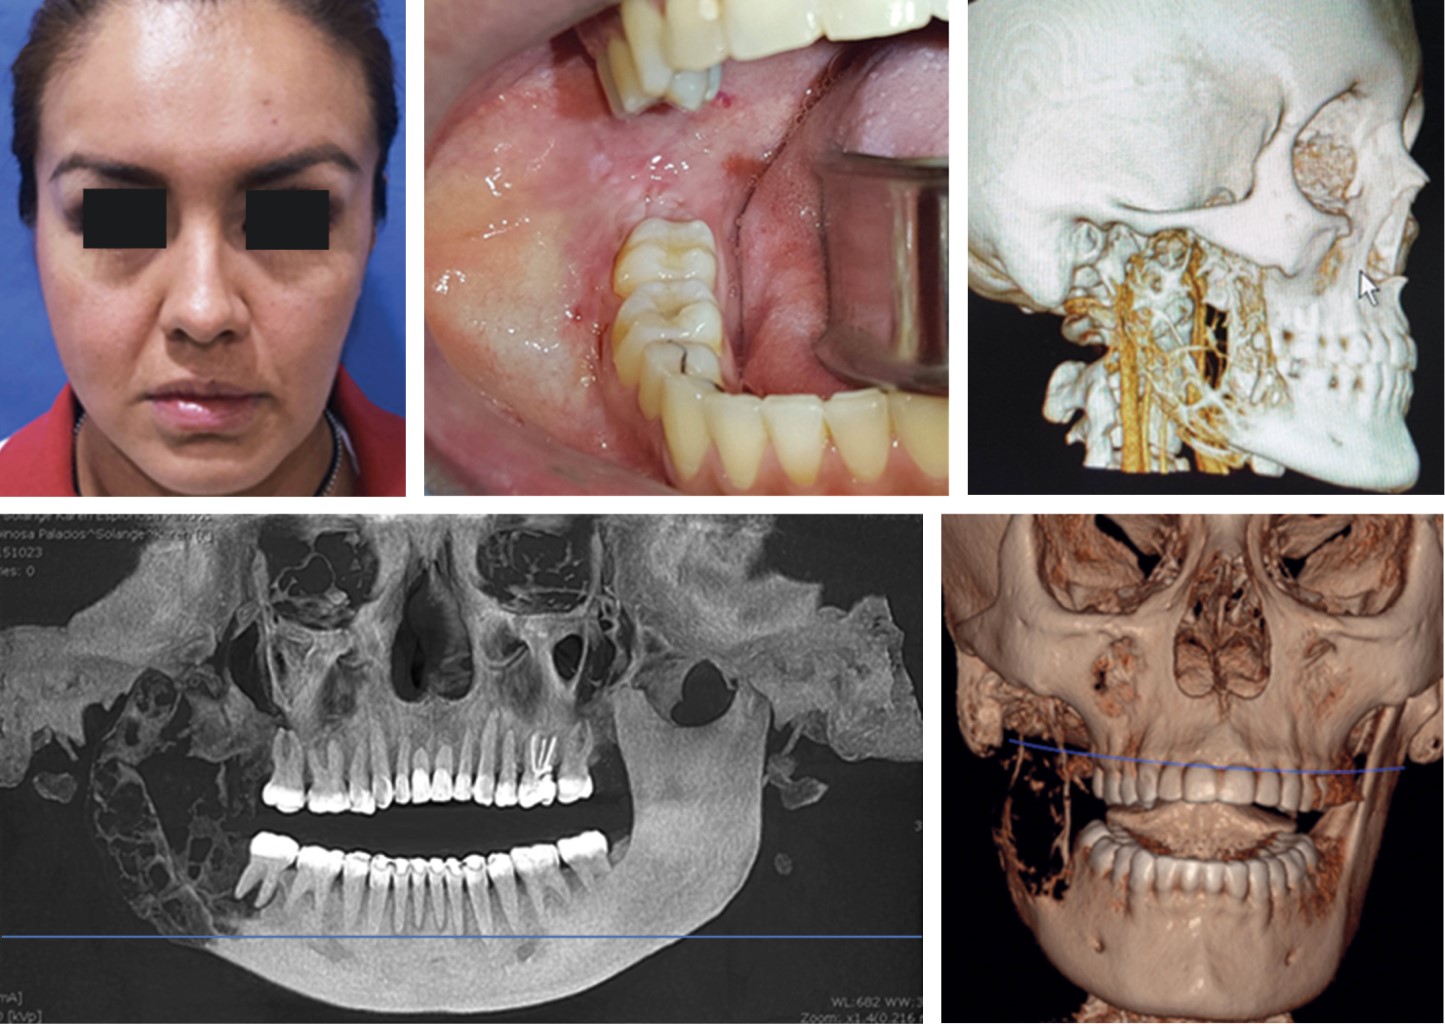

Se realizan controles postoperatorios a las seis, 12 y 24 meses, observando adecuada tonicidad musculatura facial sin evidencia de paresia clínicamente evidente, intraoralmente se aprecian tejidos blandos con adecuada forma, superficie y coloración de tejidos blandos en zona de proceso alveolar residual mandibular derecho, sin datos clínicos ni tomográficos de recidiva, conservando adecuada función masticatoria.

Se envió a la paciente para la elaboración de prótesis maxilofacial mandibular, puesto que no acepta alternativa quirúrgica de tratamiento mediante TAI autólogo por el riesgo y morbilidad quirúrgica asociada con procedimiento quirúrgico. Actualmente cuenta con seguimiento a un año, cumpliendo de manera adecuada sus funciones esenciales tales como la fonación, masticación y una adecuada tonicidad de tejidos blandos, observando adecuada simetría facial así como la presencia de una cicatriz con resultados estéticos aceptables, ya que esta situación es parte fundamental en la rehabilitación de estos pacientes sometidos a procedimientos quirúrgicos extensos (Figura 5).

Figura 5